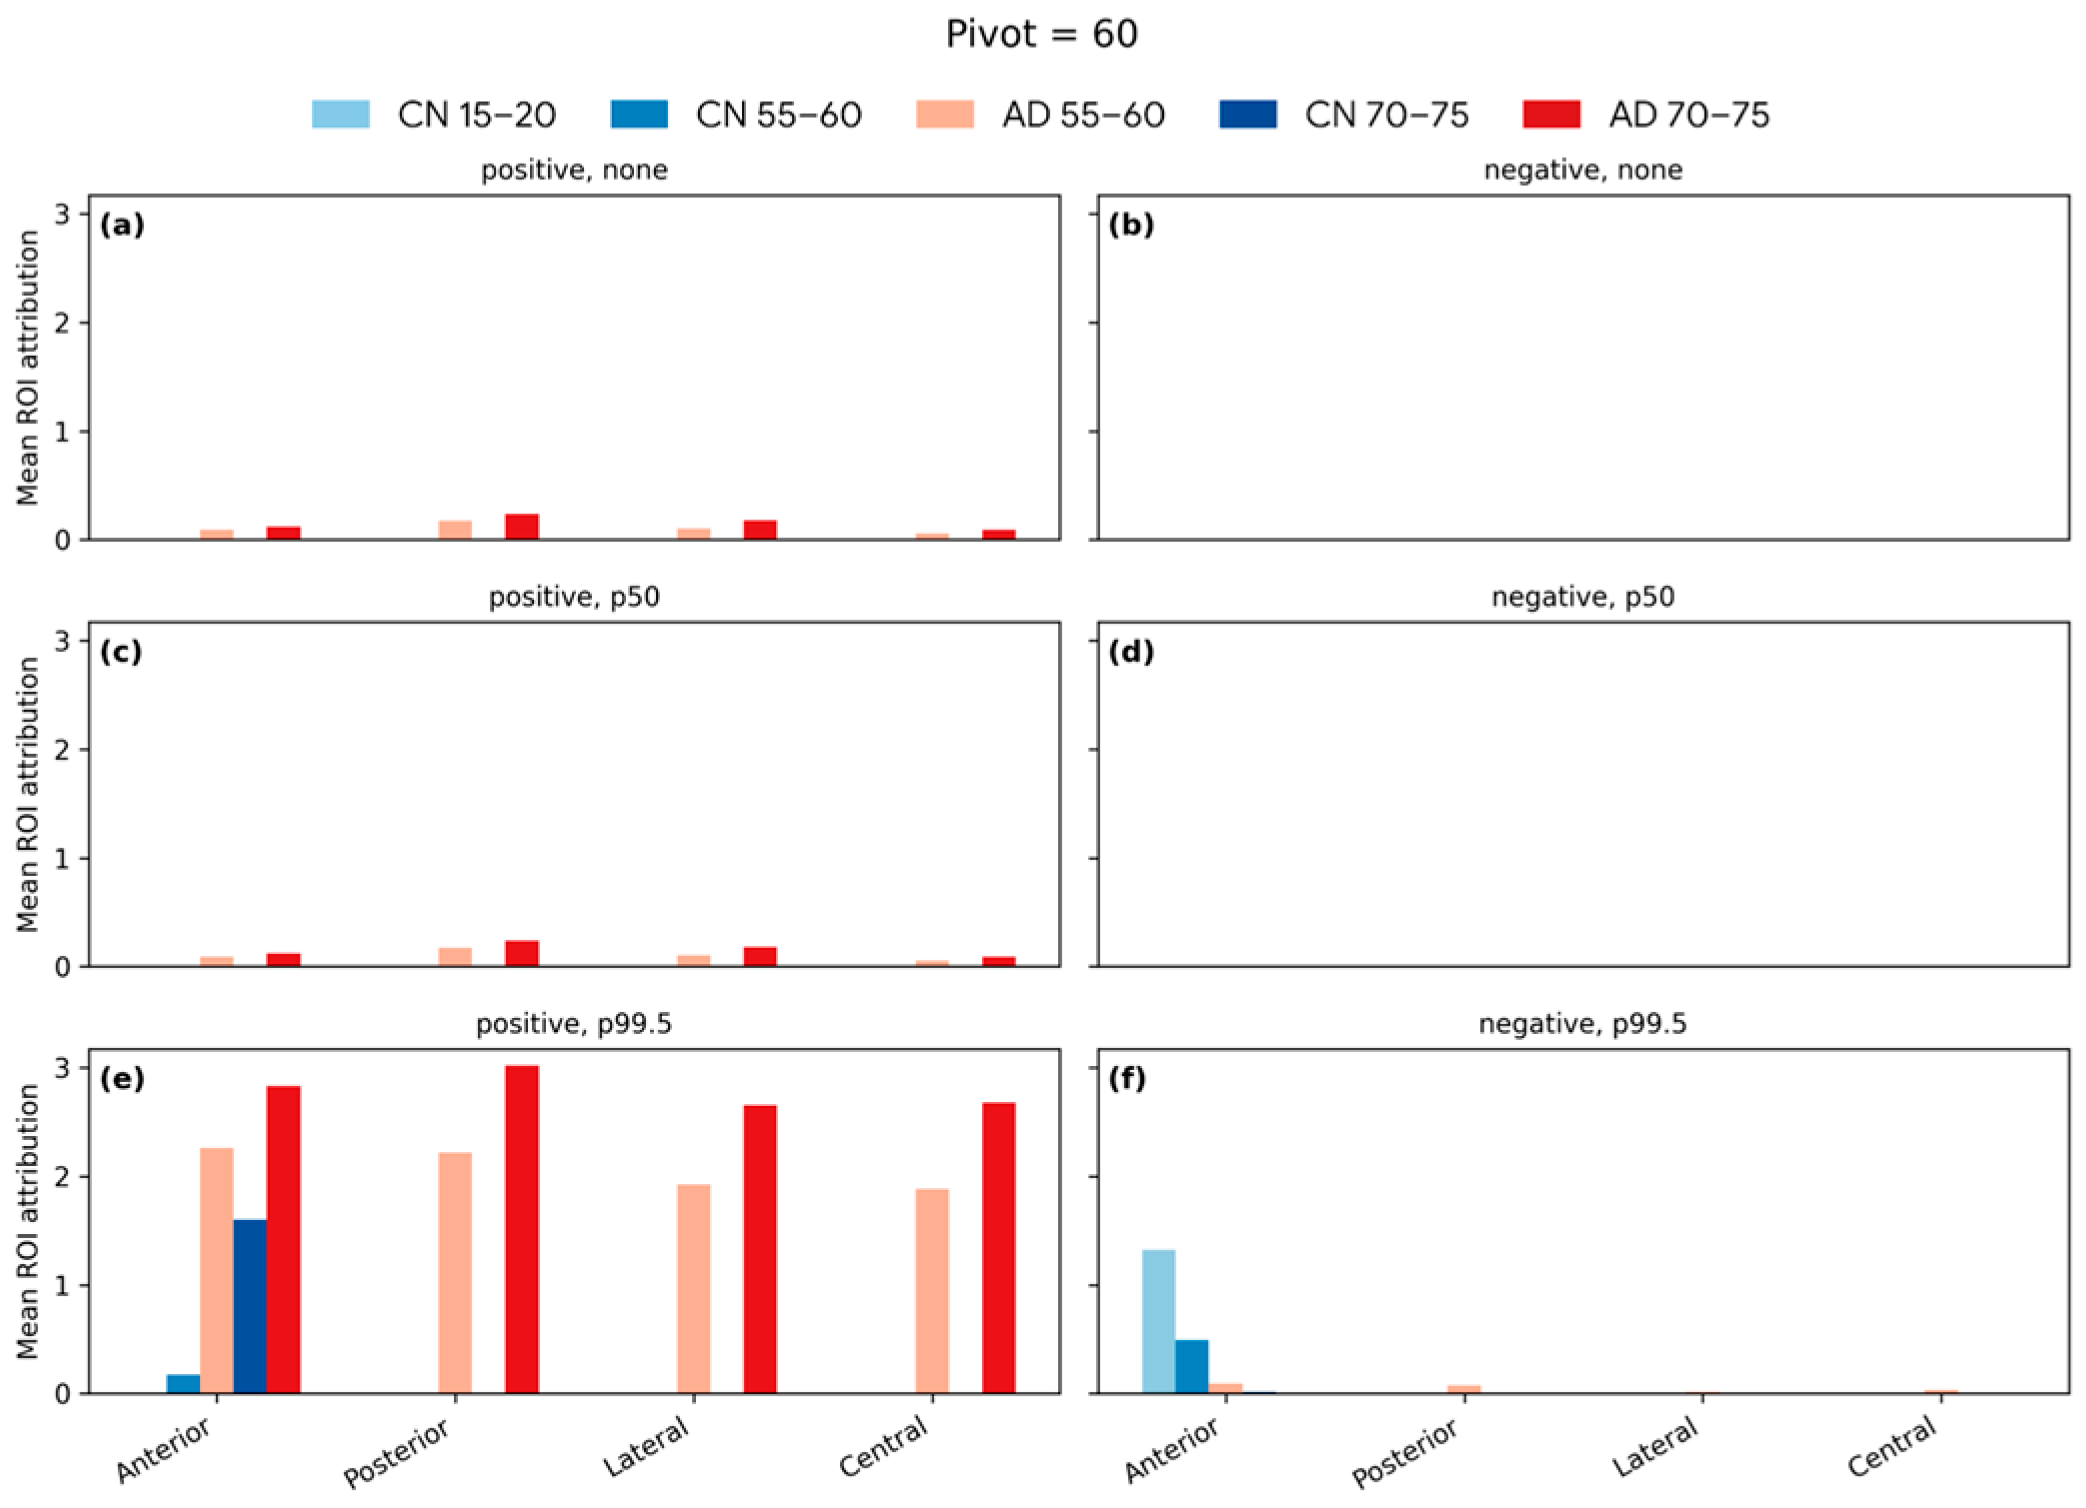

4.6. Softmax-Derived Brain Age Mapping Analysis